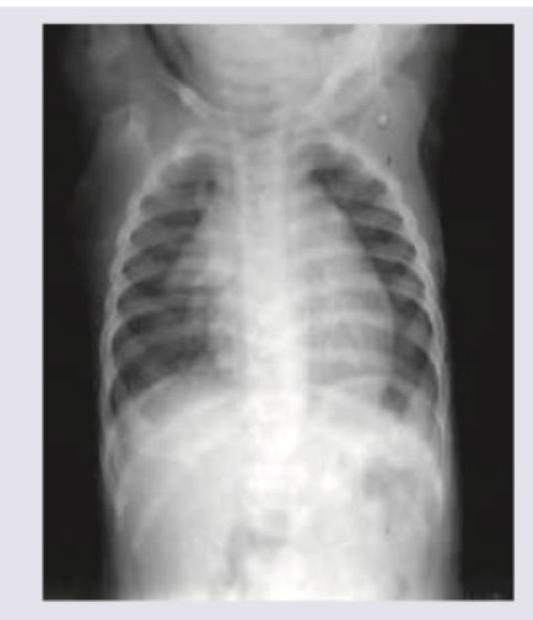

A 24-hour-old baby with severe respiratory distress was admitted to the ICU. A chest X-ray of the neonate is given. What is the most probable diagnosis?

Explanation: ***Congenital Diaphragmatic Hernia (CDH)*** - The image shows loops of **gas-filled bowel** (multiple curvilinear lucencies) in the left hemithorax, confirming the presence of abdominal contents in the chest cavity, which is pathognomonic for **CDH** (most commonly through the **Bochdalek defect**). - There is significant **mediastinal shift** to the right, leading to compression of the right lung (pulmonary hypoplasia) and severe respiratory distress in the neonate. *Congenital Pulmonary Airway Malformation (CPAM)* - CPAM (previously CCAM) usually presents as a **mass of cysts** (Type 1 is large cysts, Type 2 is small cysts) within the lung parenchyma, which are not typically associated with gas-filled loops of bowel extending from the abdomen. - While CPAM can cause mediastinal shift, the defining feature in CDH is the presence of **abdominal viscera** above the diaphragm, which is clearly visible. *Congenital lobar emphysema* - This condition involves **hyperinflation** of one or more lobes (most commonly the upper lobes) due to air trapping, resulting in an abnormally large, radiolucent lobe on X-ray. - It would show a large area of hyperlucency and possible collapse of adjacent lung tissue but would **not show intestinal loops** in the chest cavity. *Neonatal pneumonia* - Neonatal pneumonia typically presents with generalized or focal **opacification/consolidation** (white patches) rather than distinct, gas-filled cystic appearances resembling bowel loops. - While pneumonia causes respiratory distress, it does **not cause the mediastinal shift** or the visualization of abdominal organs in the chest seen here.